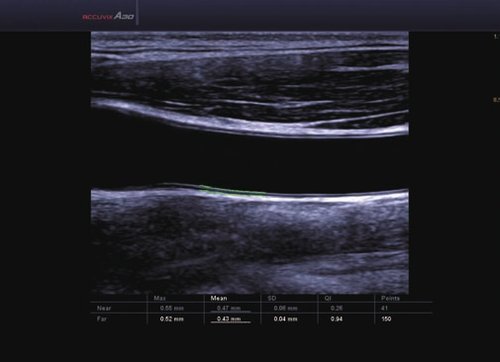

• ElastoScan™ ermöglicht eine genauere Visualisierung von Tumoren und erfasst und dokumentiert Gewebesteifheiten.